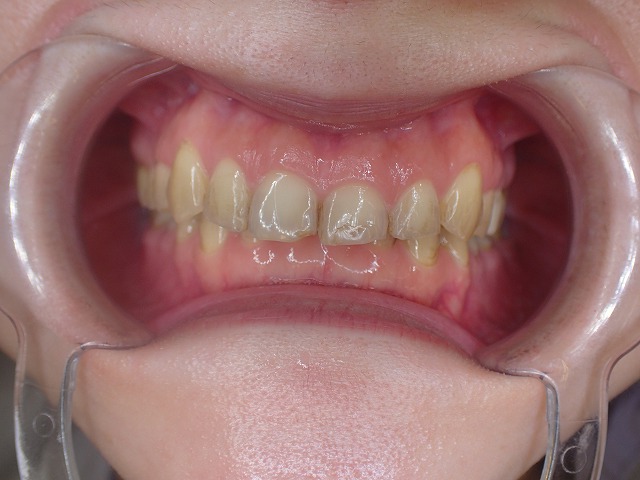

インビサライン アライナー矯正終了後 崩れたプラスチック冠をジルコニアに

咬み合わせ診査

かなり深い過蓋咬合です。(咬み合わせが深い)

●過蓋咬合

●重度の歯ぎしり

●左右不対象

●前歯の摩耗部分にレジン充填

かなりの歯ぎしりで、前歯がバリバリに削れています。

左右不対象が気がかりです。

矯正後 過蓋咬合と歯ぎしり もう少し矯正で補正してくれれば

過蓋咬合も歯列矯正で補正できたはず 決して失敗ではないが

過蓋咬合ですので、下の歯に上の歯がかぶさり

下の歯が見えません。

上顎前歯

激しく摩耗している

顎の動きで左右非対称に摩耗しているの

過蓋咬合なので上顎前歯の内側の摩耗が激しい

歯並びが左右非対称